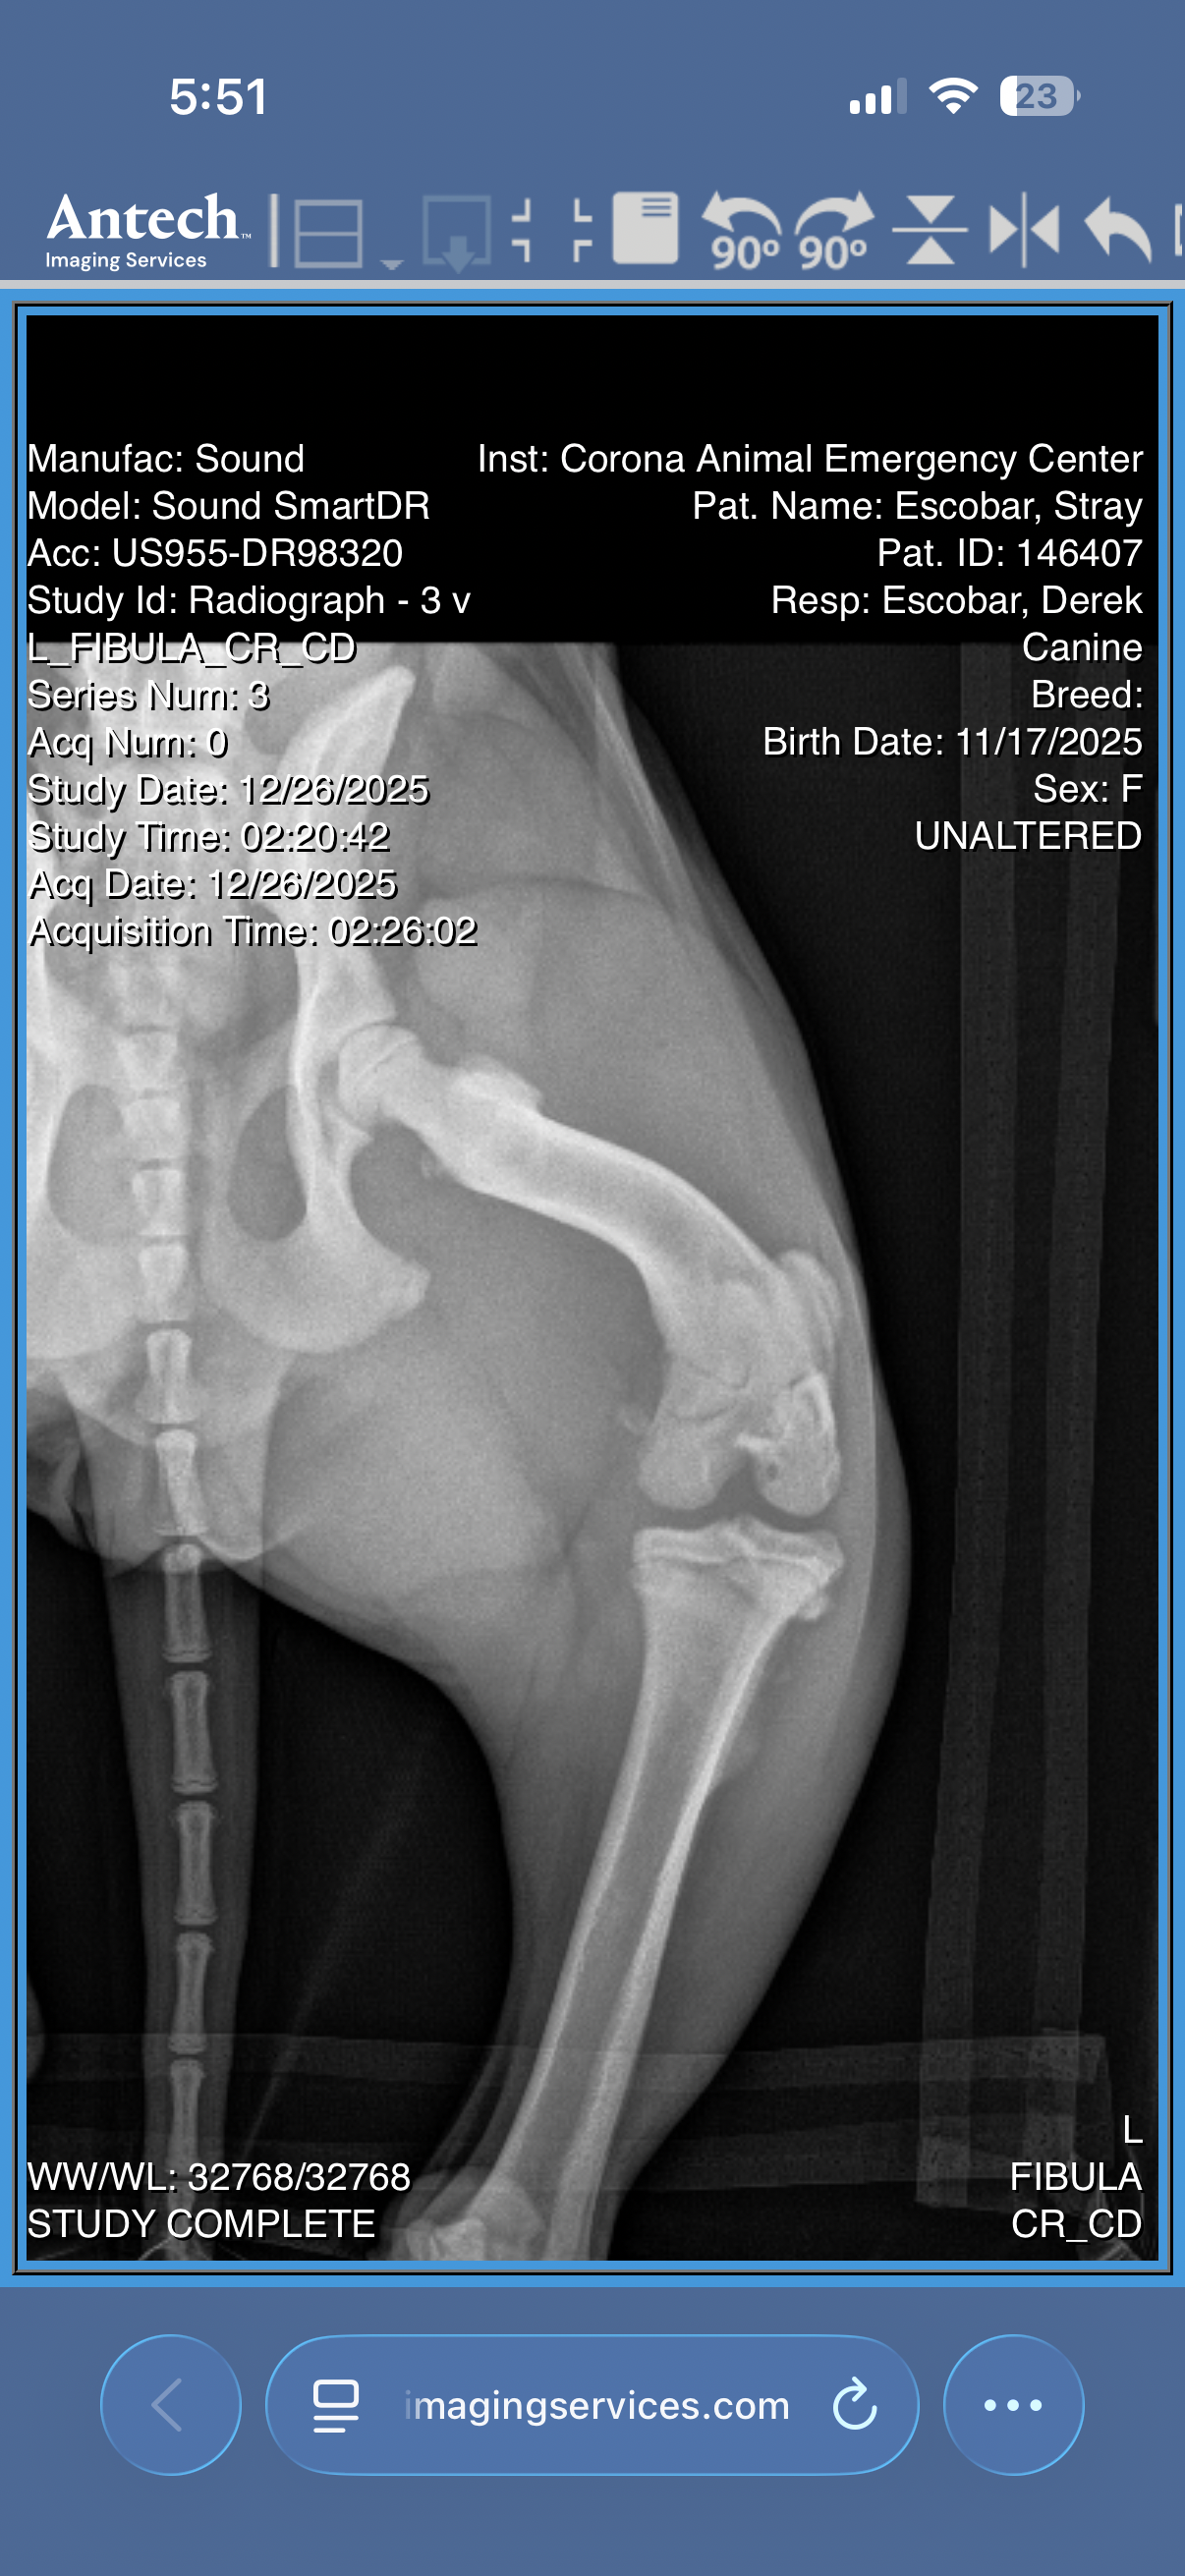

I rushed her to a 24-hour vet, and after eight long hours and $1,100 later, we learned that this sweet girl has a fractured left hind leg. The vet explained that her injury is severe, and splinting isn’t an option.